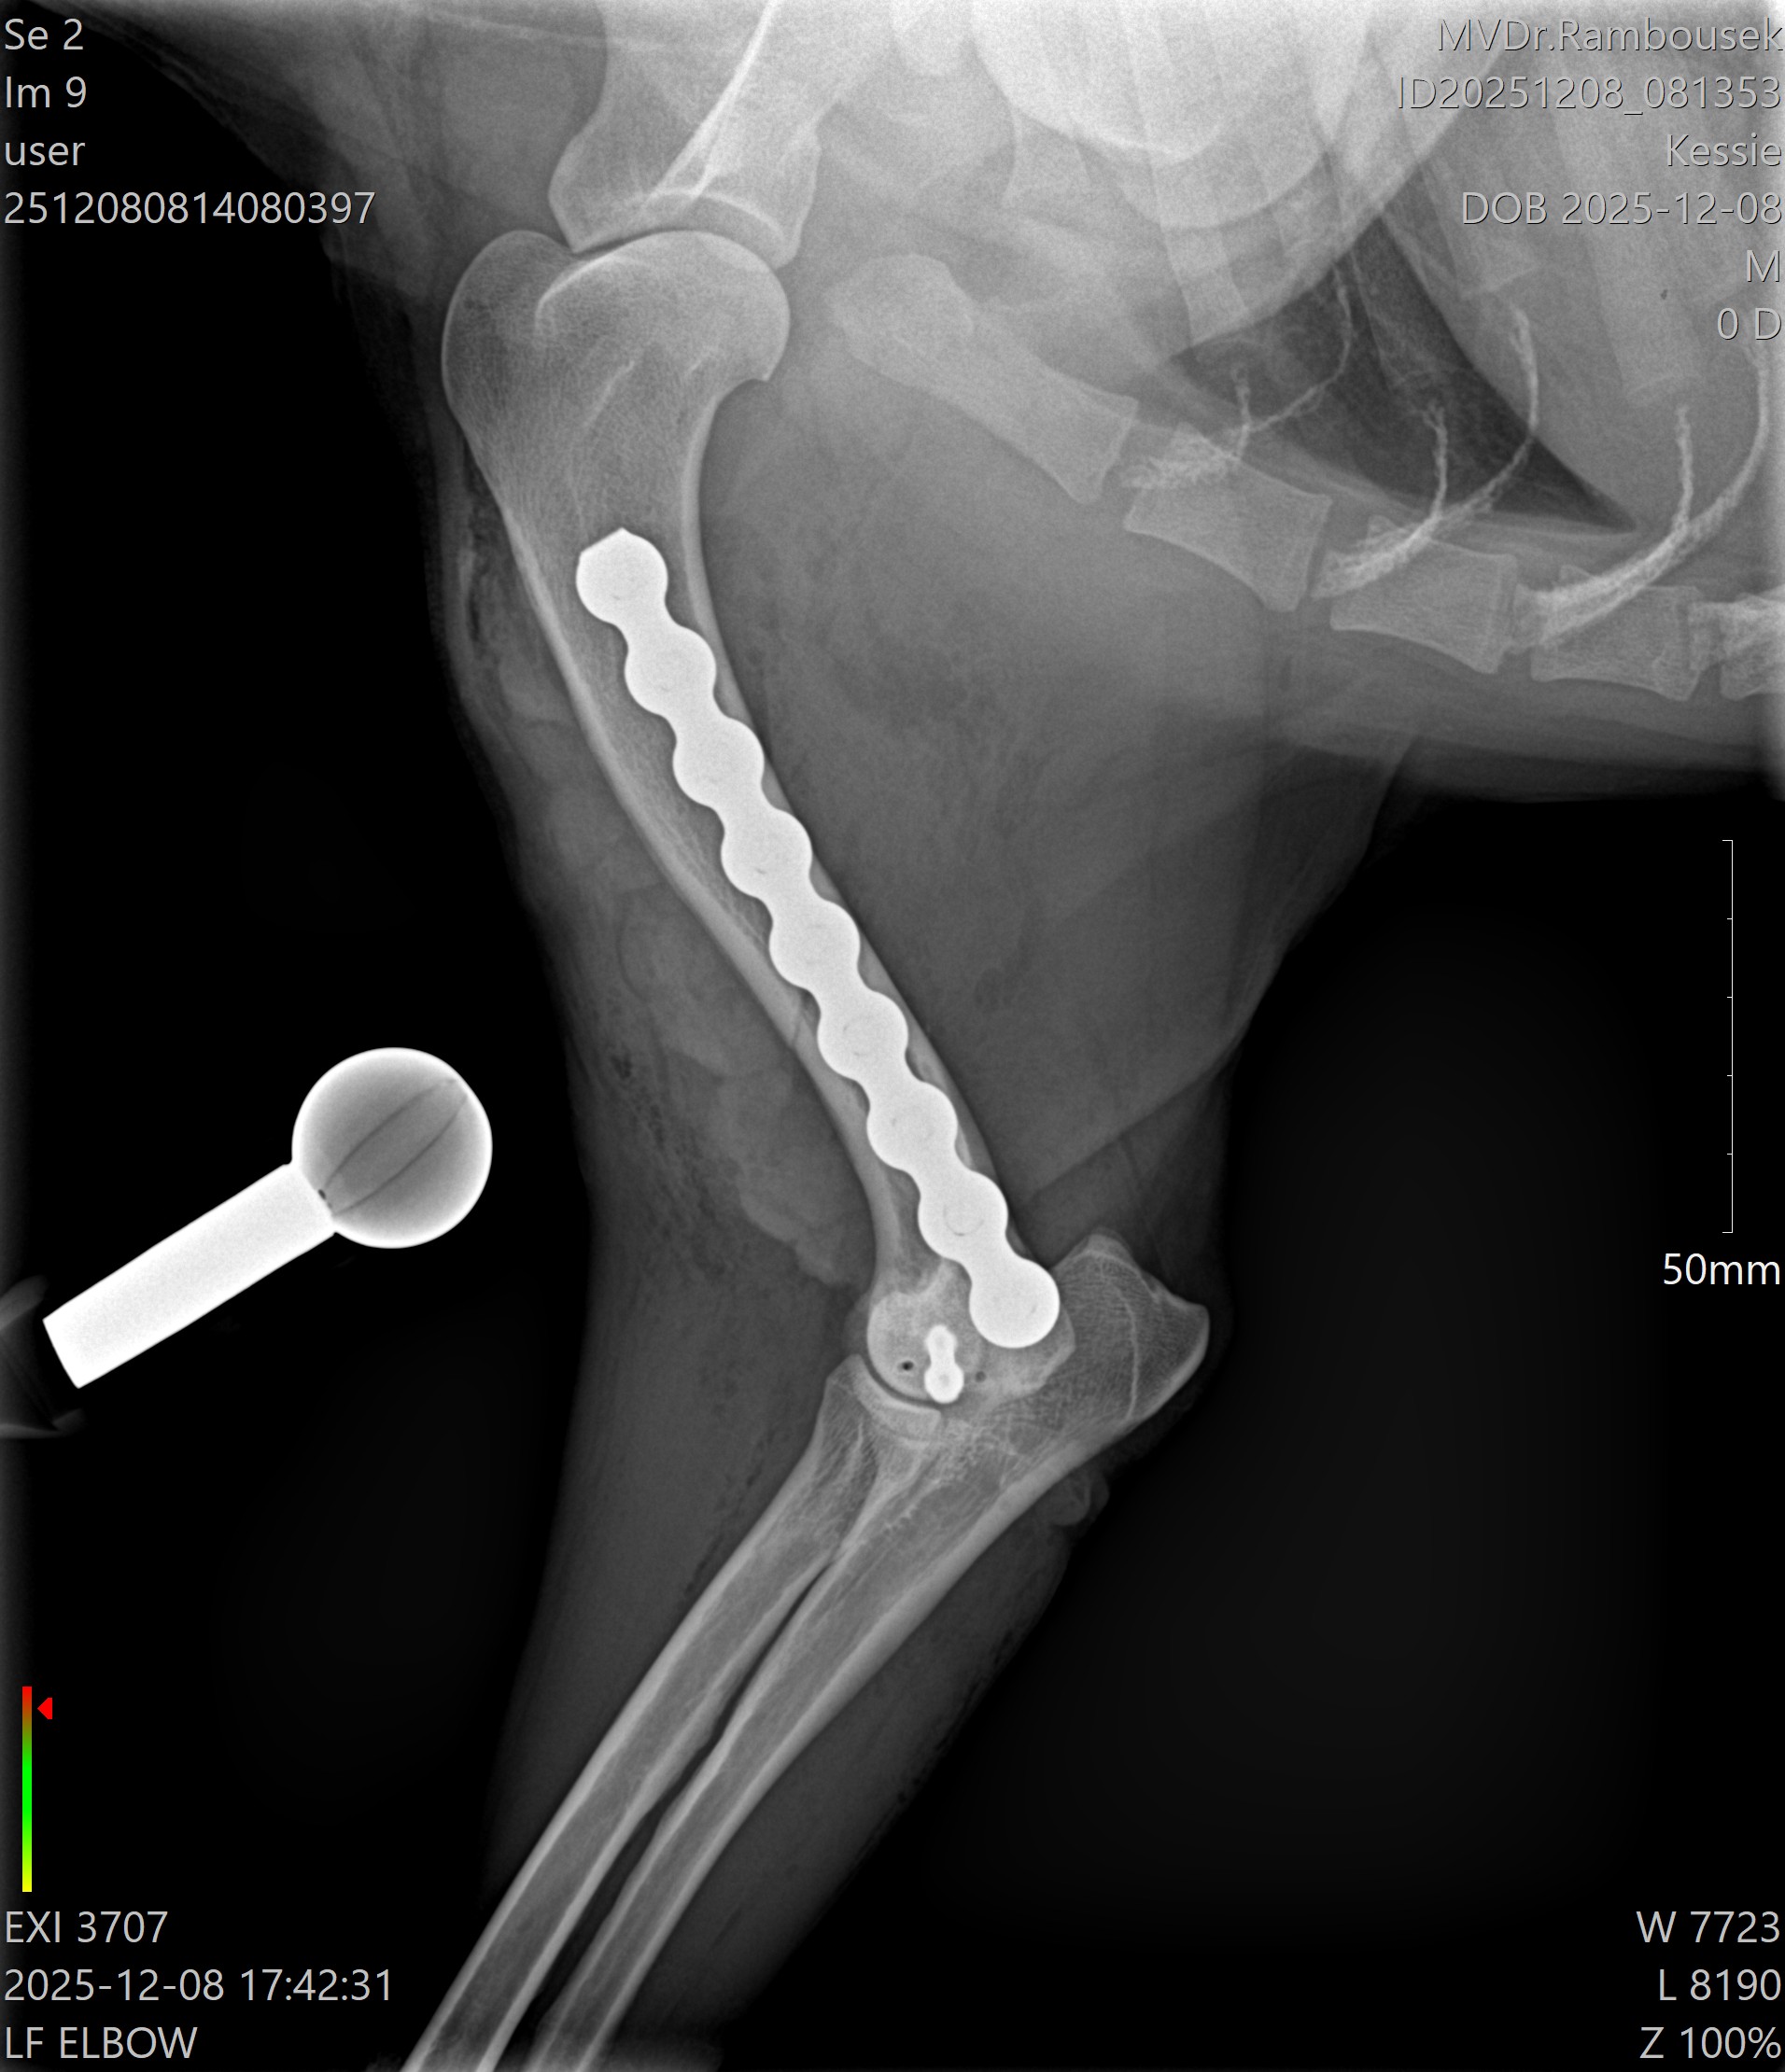

Fraktura pažní kosti - mediální kondylus

Případy z praxe

Akutní

případ